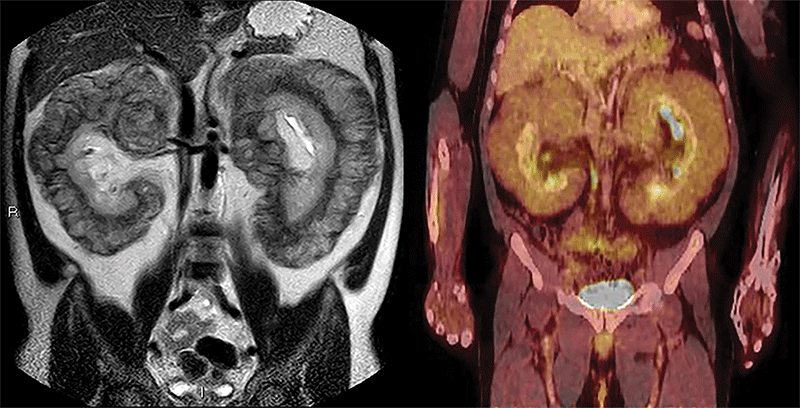

Другая статья, занявшая второе место, — «Массивное периренальное вовлечение при болезни Эрдгейма-Честера» Хорхе Поло-Сабау и Бего – а -Ло-пес- Ботет -Зулуэта . В статье приведен пример визуализации редкого заболевания. Это служит напоминанием о том, что даже при отсутствии рентгенологических признаков, отражающих наиболее частые проявления определенных болезненных состояний, радиологи все же могут рассматривать определенные диагнозы, когда это оправдано сочетанием деталей визуализации и клинических проявлений.

2-е место, занявшее второе место в 2 лучших изображениях 2022 г.

Изображения 47-летнего мужчины с усиливающимся отеком нижних конечностей и хроническим вздутием живота. Слева: коронарная однократная Т2-взвешенная МРТ показывает массивную двустороннюю периренальную инфильтрацию мягкотканными образованиями. Справа: ПЭТ/КТ-сканирование фтордезоксиглюкозы-18 показывает слабое поглощение паранефральными массами и смещение печени вверх.